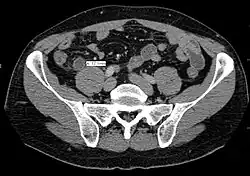

Coronal CT scan of a person initially suspected of having appendicitis because of right-sided pain. The CT shows in fact an enlarged inflamed gallbladder that reaches the right lower part of the abdomen.